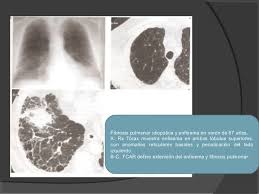

Salud Fibrosis Pulmonar La Enfermedad Que Se Confunde Con El Asma Y Que Es Peligrosa Para Tu Salud

Salud Fibrosis Pulmonar La Enfermedad Que Se Confunde Con El Asma Y Que Es Peligrosa Para Tu Salud from www.ecestaticos.com